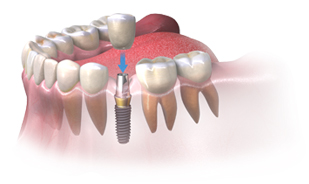

Înlocuirea unui singur dinte: Atunci când e vorba de înlocuirea unui singur dinte lipsă, medicul va introduce un implant în os și va fixa o coroană personalizată pe acesta. Astfel, veți redobândi aspectul natural și funcționalitatea dintelui dumneavoastră.

ÎNAINTE

DUPĂ